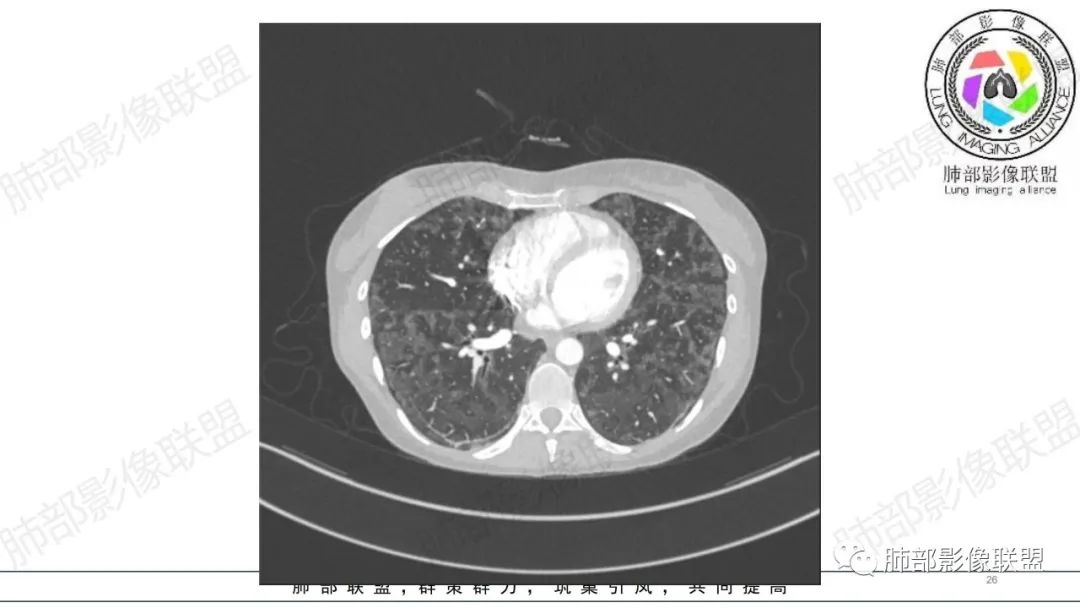

影像资料

34岁女性患者,“哮喘”病史30年,近期有可疑刺激性气体吸入史;因乏力半年,咳嗽、憋气、发热4天就诊;6.1CT提示双肺广泛毛玻璃影及粟粒样结节,胸膜下闲置及血管周闲置,可见树丫征,部分小叶间隔增厚。考虑:1.过敏性肺泡炎,有可疑刺激气体接触史,胸膜下闲置,广泛毛玻璃影,地图样分布,粟粒结节边界模糊,支持过敏性肺泡炎,但糖皮激素治疗效果不佳,且动态复查血常规血红蛋白进行性降低,过敏性肺泡炎 不符合;2.肺含铁血黄素沉积症:患者30“哮喘”病史,可能为肺含铁症状,肺部CT提示双肺弥漫毛玻璃影及粟粒结节影,中下肺明显,肺底部分小叶间隔增厚,近期咳嗽、憋气、发热,血常规血红蛋白进行性下降,考虑肺含铁急性期症状,但临床无咯血症状,肺含铁不典型。综合考虑:肺含铁血黄素沉积症>过敏性肺泡炎。

年轻女性 ,急性喘息发热,肺部影像弥漫磨玻璃密度,部分细小腺泡结节,胸膜下黑线显示,短期复查,病变密度增高,下肺明显,血管周围肺组织累及较少、且逐渐成小叶间隔分布。考虑弥漫肺泡内病变,并经淋巴道转移,下肺比上肺明显,多为免疫细胞功能下肺较强。1.过敏性肺泡炎,有相关病史,三层密度特点、头尾测分布,符合。2 肺泡微石症,多有钙化,且缓慢起病,病程不太符合,放待排。3 吸入相关肺损伤,有病史,疾病演变过程也符合渗出-肉芽肿改变,建议详细询问病史。4 感染性病变,结核?病变气道分布为主,如此弥漫且没有树丫不符合。5.巨细胞病毒,可以磨玻璃 结节 改变,没有免疫缺陷病史。最后考虑吸入所致 1过敏性肺泡炎、吸入性肺损伤 鉴别肺泡微石症。

血管内大B

同意血管大B

肺内气腔磨玻璃结节,肝脾肿大,治疗后间质改变,弥漫大B可能